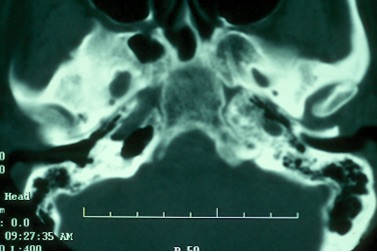

The petrous apex is a relatively inaccessible area that can occasionally harbor serious disease. Disease processes that usually cause symptoms are typically inflammatory or neoplastic in nature. Petrous apex lesions typically cause nonspecific symptoms such as headache, but as the lesion becomes more extensive, adjacent structures such as cranial nerves can become involved. A common early and specific sign of a petrous apex process is abducens palsy. Current imaging techniques can usually provide enough supplemental information to allow a focused plan of treatment. It is important to determine whether a petrous apex lesion can be observed or, if surgical treatment is required, whether a drainage or excision is required. There are various available surgical approaches to the petrous apex. The choice depends on the status of hearing function as well as the suspected pathology, which will dictate whether a drainage or excisional procedure is required.

- Summarize the types of pathology that can occur in the petrous apex, the imaging required, and proper interpretation of information so that a proper differential diagnosis can be formulated.